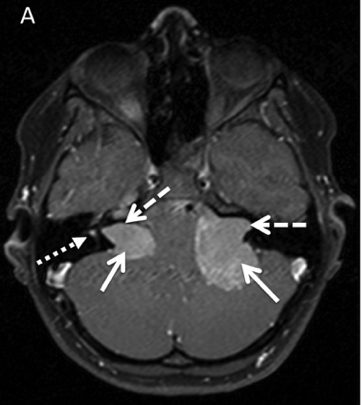

• La neurofibromatose de type II (NF2) est une maladie génétique causée par un gène défectueux auquel il manque une protéine nécessaire pour combattre les tumeurs. La NF2 se caractérise généralement par le développement de tumeurs bilatérales le long des nerfs vestibulaires (nerfs de l’équilibre) et des nerfs auditifs. Ces tumeurs se situent juste au niveau du tronc cérébral et, par conséquent, à mesure qu’elles grossissent, elles portent atteinte aux nerfs voisins qui concernent de nombreuses fonctions corporelles. Les personnes atteintes de NF2 présentent fréquemment plusieurs tumeurs le long de leur colonne vertébrale ainsi que sur les nerfs situés derrière les yeux.

Les tumeurs présentes sur les nerfs auditifs et de l’équilibre, connues sous le nom de schwannomes vestibulaires, entraînent généralement la surdité d’une oreille ou des deux. Les personnes atteintes de NF2 peuvent également souffrir de problèmes de déglutition, d’acouphènes pouvant s’avérer débilitants, de maux de tête et de nombreuses autres difficultés connexes. Les lésions produites sur les nerfs situés derrière les yeux peuvent provoquer des troubles de la vision ou la cécité. Les tumeurs situées le long de la moelle épinière sont à l’origine de graves problèmes de mobilité, comme un mauvais équilibre ou l’incapacité de marcher.